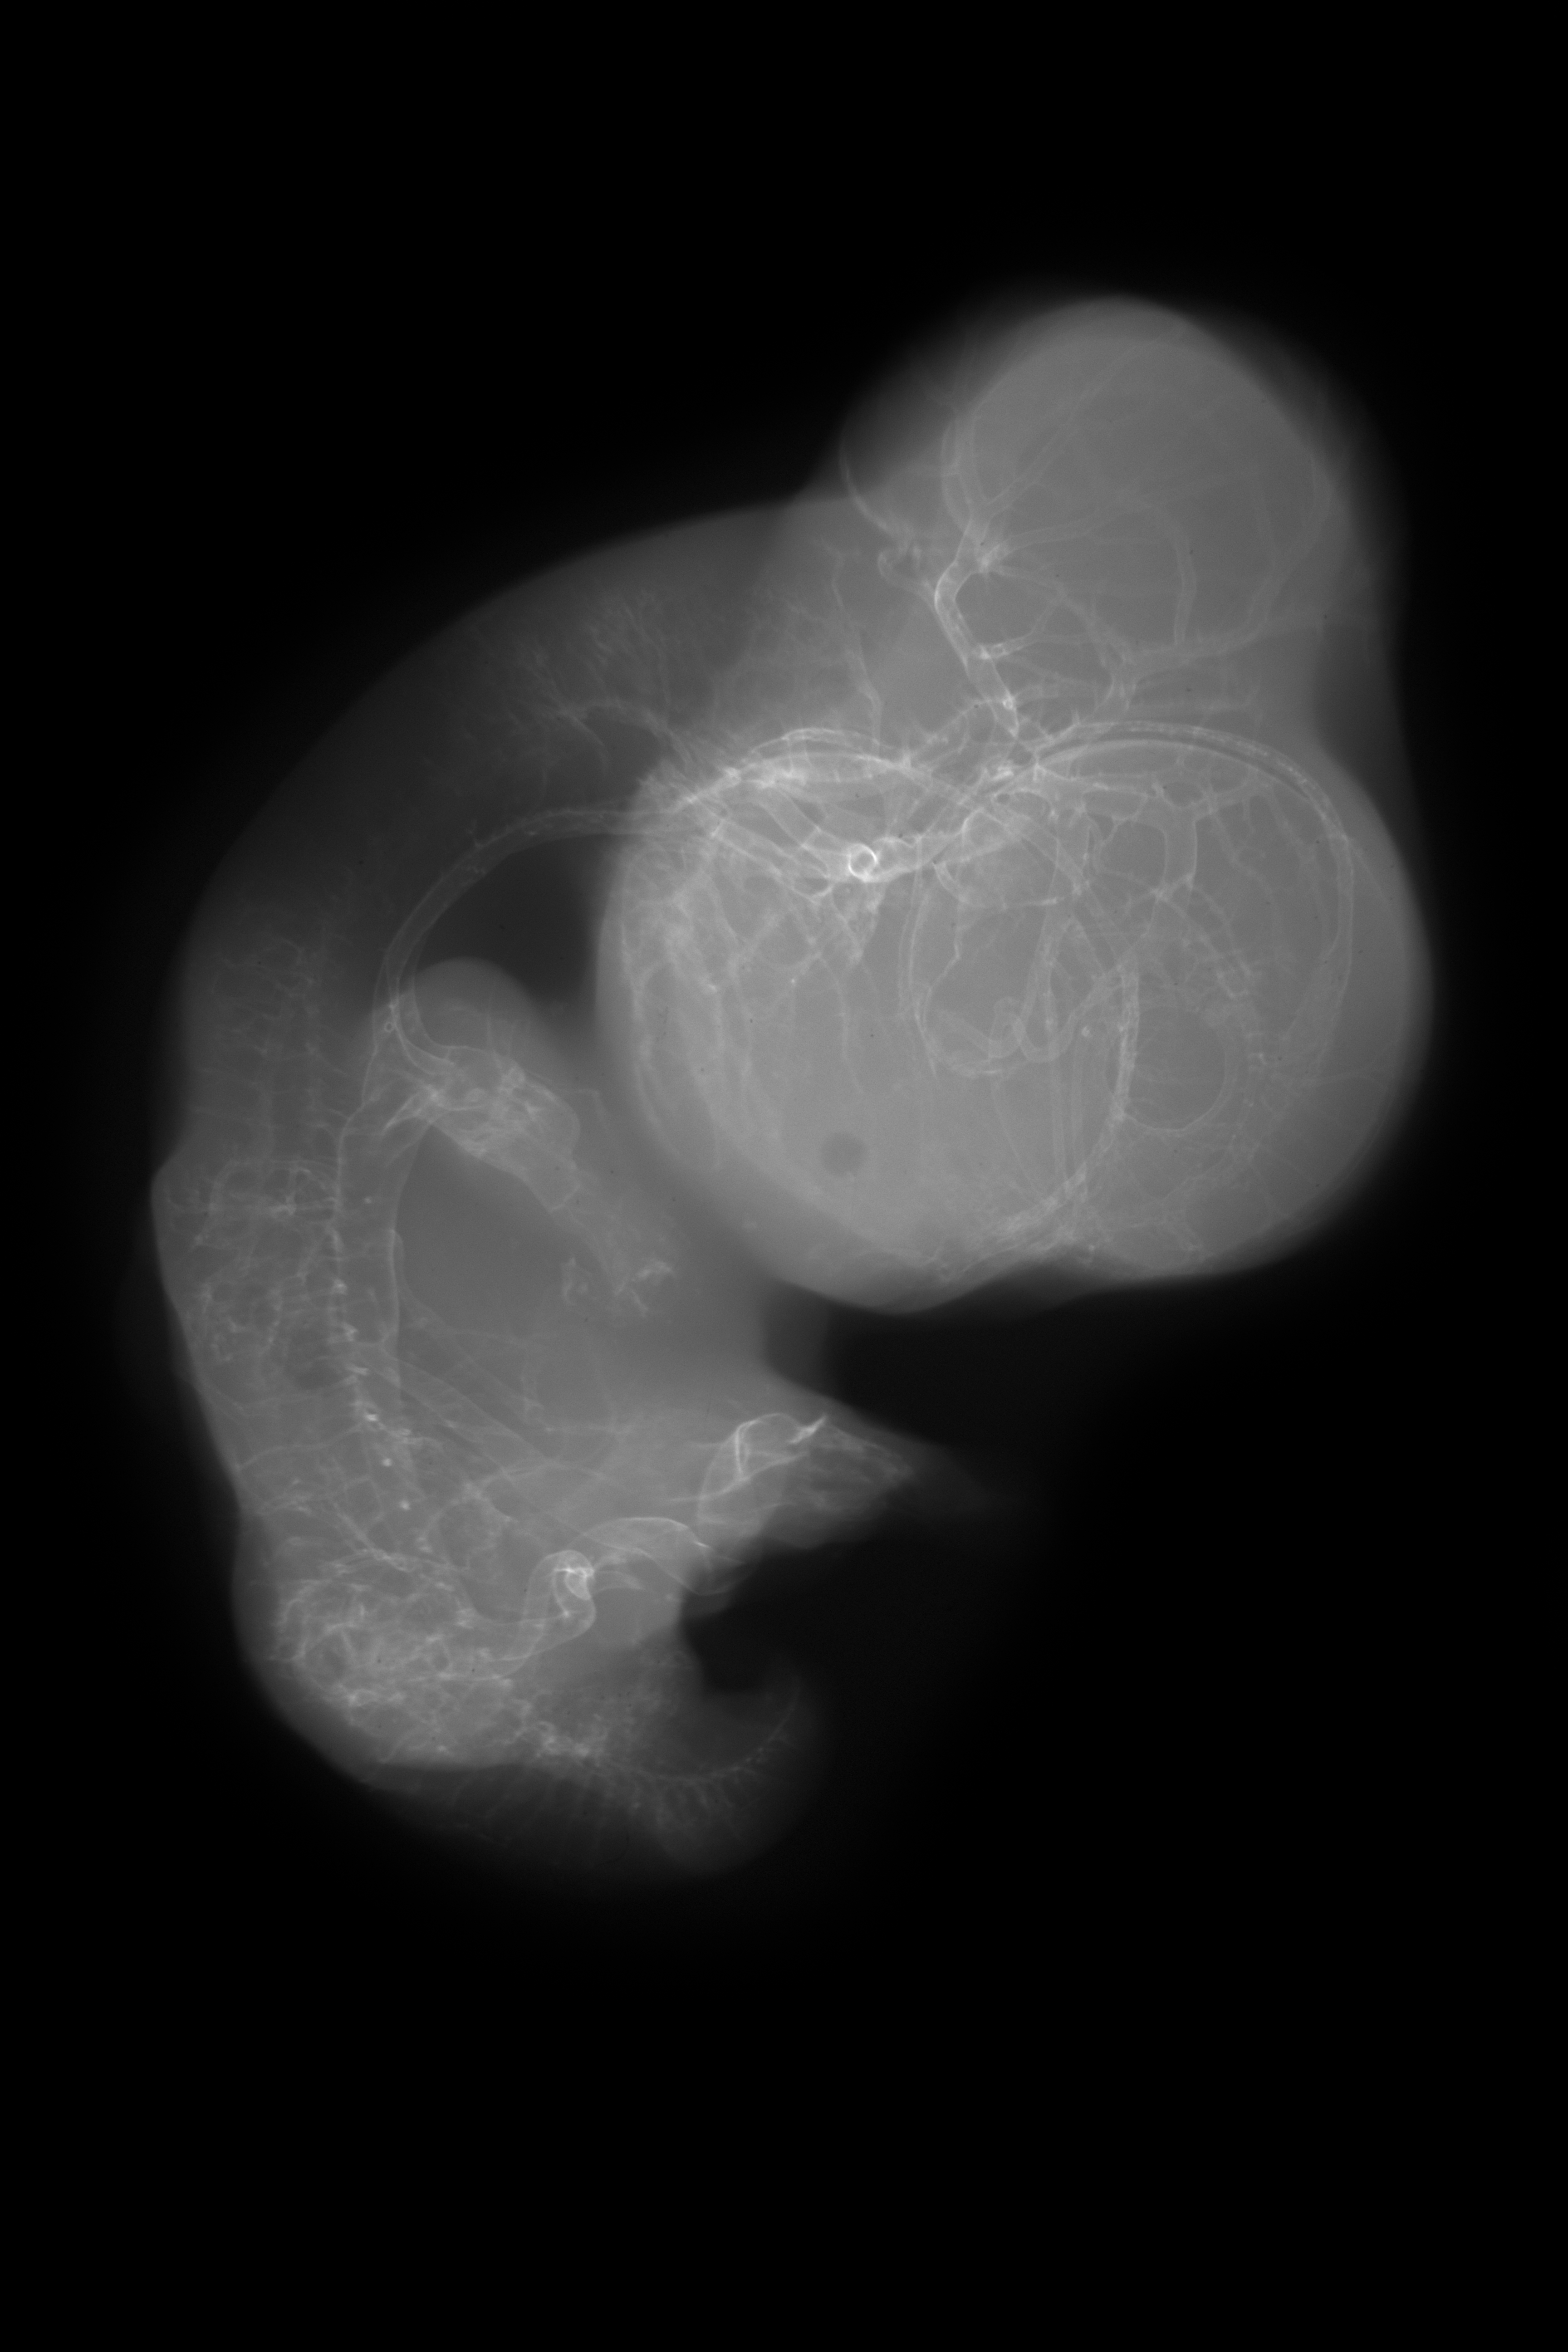

Chick Embryo Microangiography

Hamburger-Hamilton (HH) Stage 30 (approx. 6.5 days)

X-Ray Micrographs